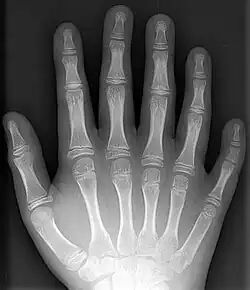

- Polydactyly – additional fingers or toes[4]

- Syndactyly – webbing between the fingers or toes[4]